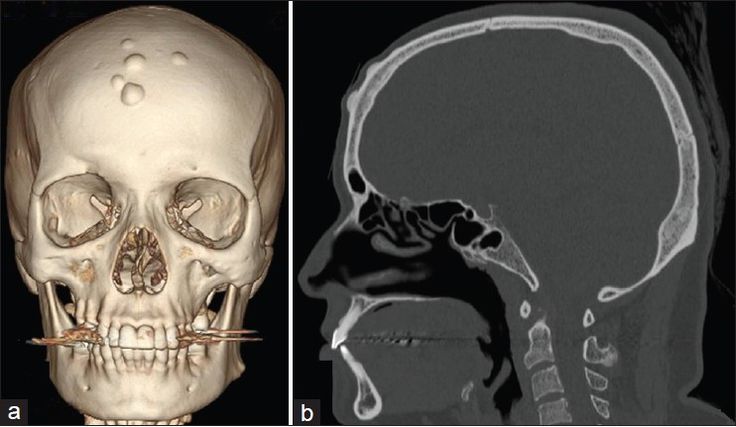

Остеома Кости Фото